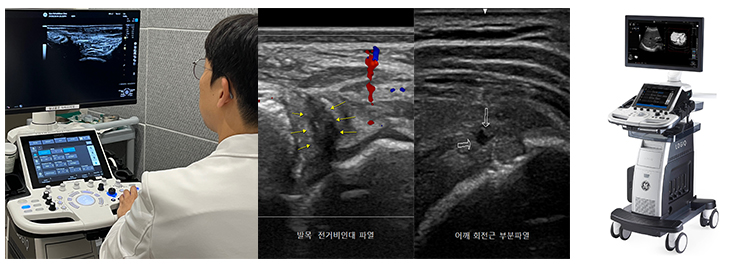

근골격계 초음파검사(Musculoskeletal Ultrasonography)

이럴 때, 근골격계 초음파 검사는 X-ray에 나타나지 않는 근육과 인대의 질환을 MRI보다 훨씬 저렴한 비용으로 정확하게 진단할 수 있는 유용한 검사 방법입니다. 또한 초음파 검사는 인체에 무해하여 산모나 소아도 안전하게 시행할 수 있습니다.

본원에서는 풍부한 임상 경험과 자격을 갖춘 전문의(대한초음파학회 검사인증의)가 초음파 검사를 시행하며, 이를 통해 회전근개 파열, 오십견, 테니스 엘보, 아킬레스건염, 발목 인대 파열, 족저근막염 등 다양한 병변을 정확하게 진단할 수 있습니다. 또한 초음파를 이용해 신경과 혈관 등 위험한 부위를 구분함으로써, 병변 부위에만 정확하게 주사를 놓을 수 있어 더욱 안전하고 효과적인 치료를 제공합니다.

검사 시간은 5~10분 정도로 매우 짧으며, 의료진과 환자가 함께 관절을 직접 움직여가며 인대나 근육의 이상이 있는 부위를 즉시 확인할 수 있습니다.